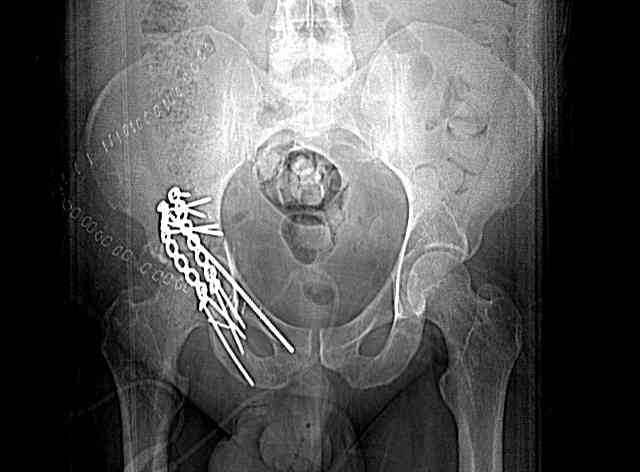

The 2nd example is of a motorcyclist with a transverse fracture-dislocation...he had a closed attempted reduction and placed in traction but the manipulative reduction was not concentric (not unusual for this injury pattern)...so the traction was adjusted to be just enough to disengage the head from the fracture (12#) until he could be cleared for surgery one day after injury...he was treated "urgently" then with a prone KL, clean the fracture, reduce and clamp it, screw it, support with a balanced plate, close, and enjoy...2-3hours, 400cc EBL, blah, blah, blah..